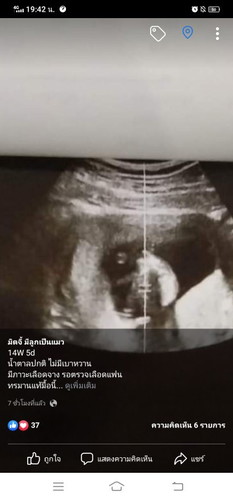

เราท้อง14W5d คุณหมอซาวด์เจอแค่นี้ ปกติรึปล่าวคะ กังวลมาก

ภาพไม่ชัดเจนเลยค่ะ มีใบซาวไหม ดูขนาดน้องในใบซาวเทียบเกณฑ์เอาได้ค่ะ ดูคำว่า CRLนะคะ